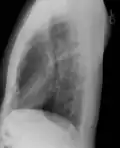

Рентгенограмма грудной клетки в боковой проекции.